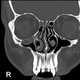

Fracture with retro-orbital hematoma

Unilateral exophthalmos